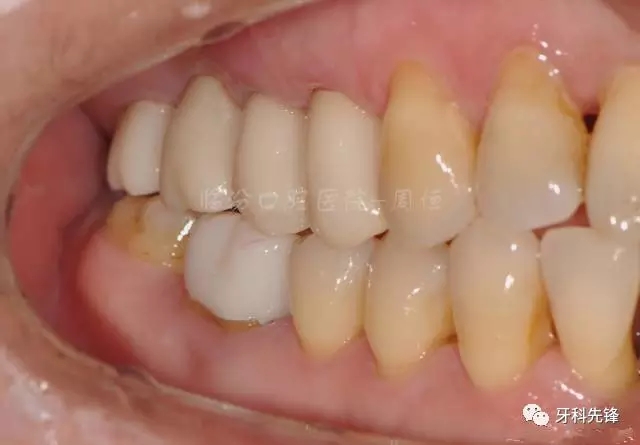

圖22烤瓷冠咬頜照

640.webp (26).jpg

圖29術后頰面照

640.webp (33).jpg